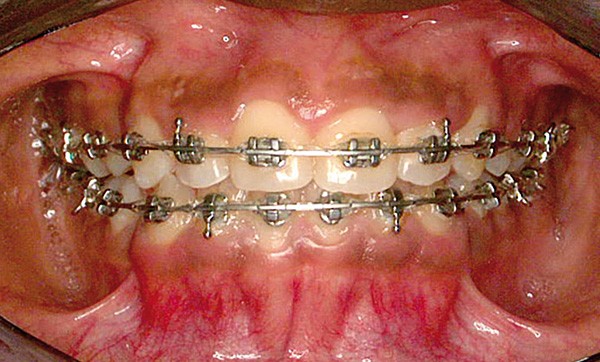

Les photographies endo-buccales sont celles de face, latérales droite et gauche, occlusales arcades maxillaire et mandibulaire.